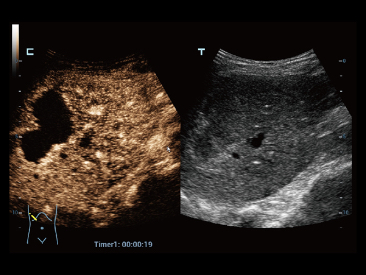

Resona 7

Mindray? ??? ??? ?? ??? ???? ??? ?? ??? ??? ????? ??? ????. ?? ???? ZONE Sonography? ??? ???? ?? Resona 7? ??? ZST+ ???? ?? ?? ? ?? ??? ????? ?? ??? ??? ??? ? ?? ????.

?? Resona 7? ???? ??? ?? ???? ??? ??? ???? ??? ?? ???? V Flow? ?? CNS ??? ?? 3D ??? ???? ?? ???? ?? ??? ?? ?? ?? ??? ??????. ???? ??? ??? ?? ?? ??? ??? ?? ?? ??? ??? Resona 7? ??? ???? ???? ??? ??? ??? ????.